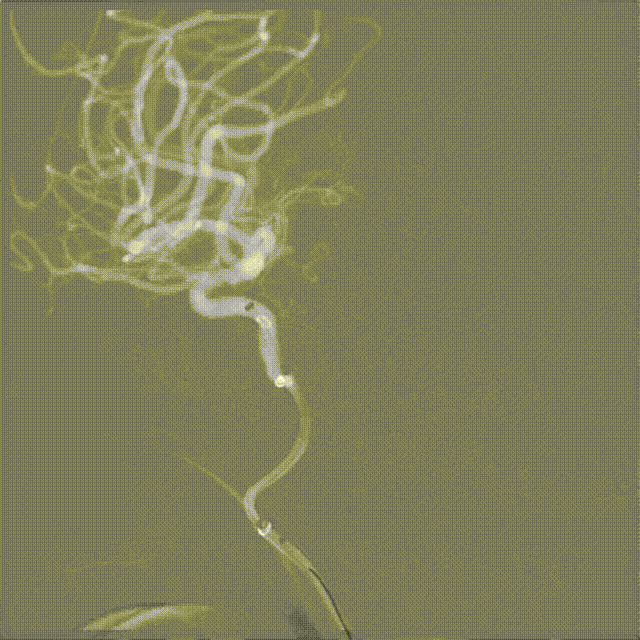

造影显示右侧大脑中动脉起始部闭塞

8F 支撑导管 (8D090cm) 置于RC1,5F 132cm 颅内血栓抽吸导管达RC4。

微导丝穿越闭塞病变,微导管造影。

释放取栓支架,造影提示血管闭塞。

取栓,复查造影。

栓子逃逸。

5F 132cm 颅内血栓抽吸导管进行通路建立。

血管再通,血流恢复。静脉期未见造影剂瘀滞、延迟清除现象,动脉支配区域染色基本正常,TIMI 3级。